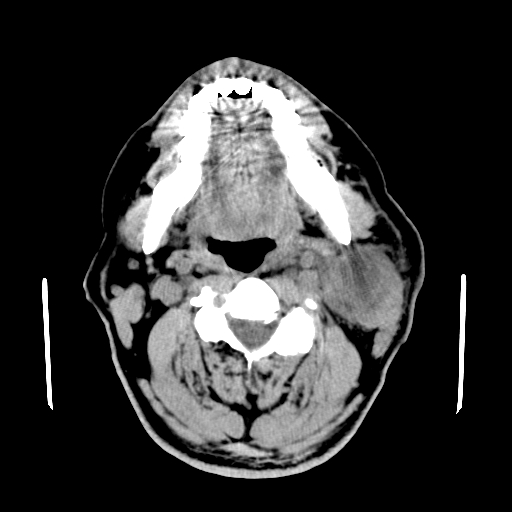

以下是引用卜一在2007-8-6 21:23:00的发言:[br]定位:左侧胸锁乳突肌内侧 颌下腺下后方。特征:弥漫性生长 软组织密度肿块,界限不清,内隐约见低密度坏死。考虑:神经源性肿瘤或血管源性肿瘤。

以下是引用wangzhanshuang在2007-8-6 21:08:00的发言:[br]腮腺混合瘤